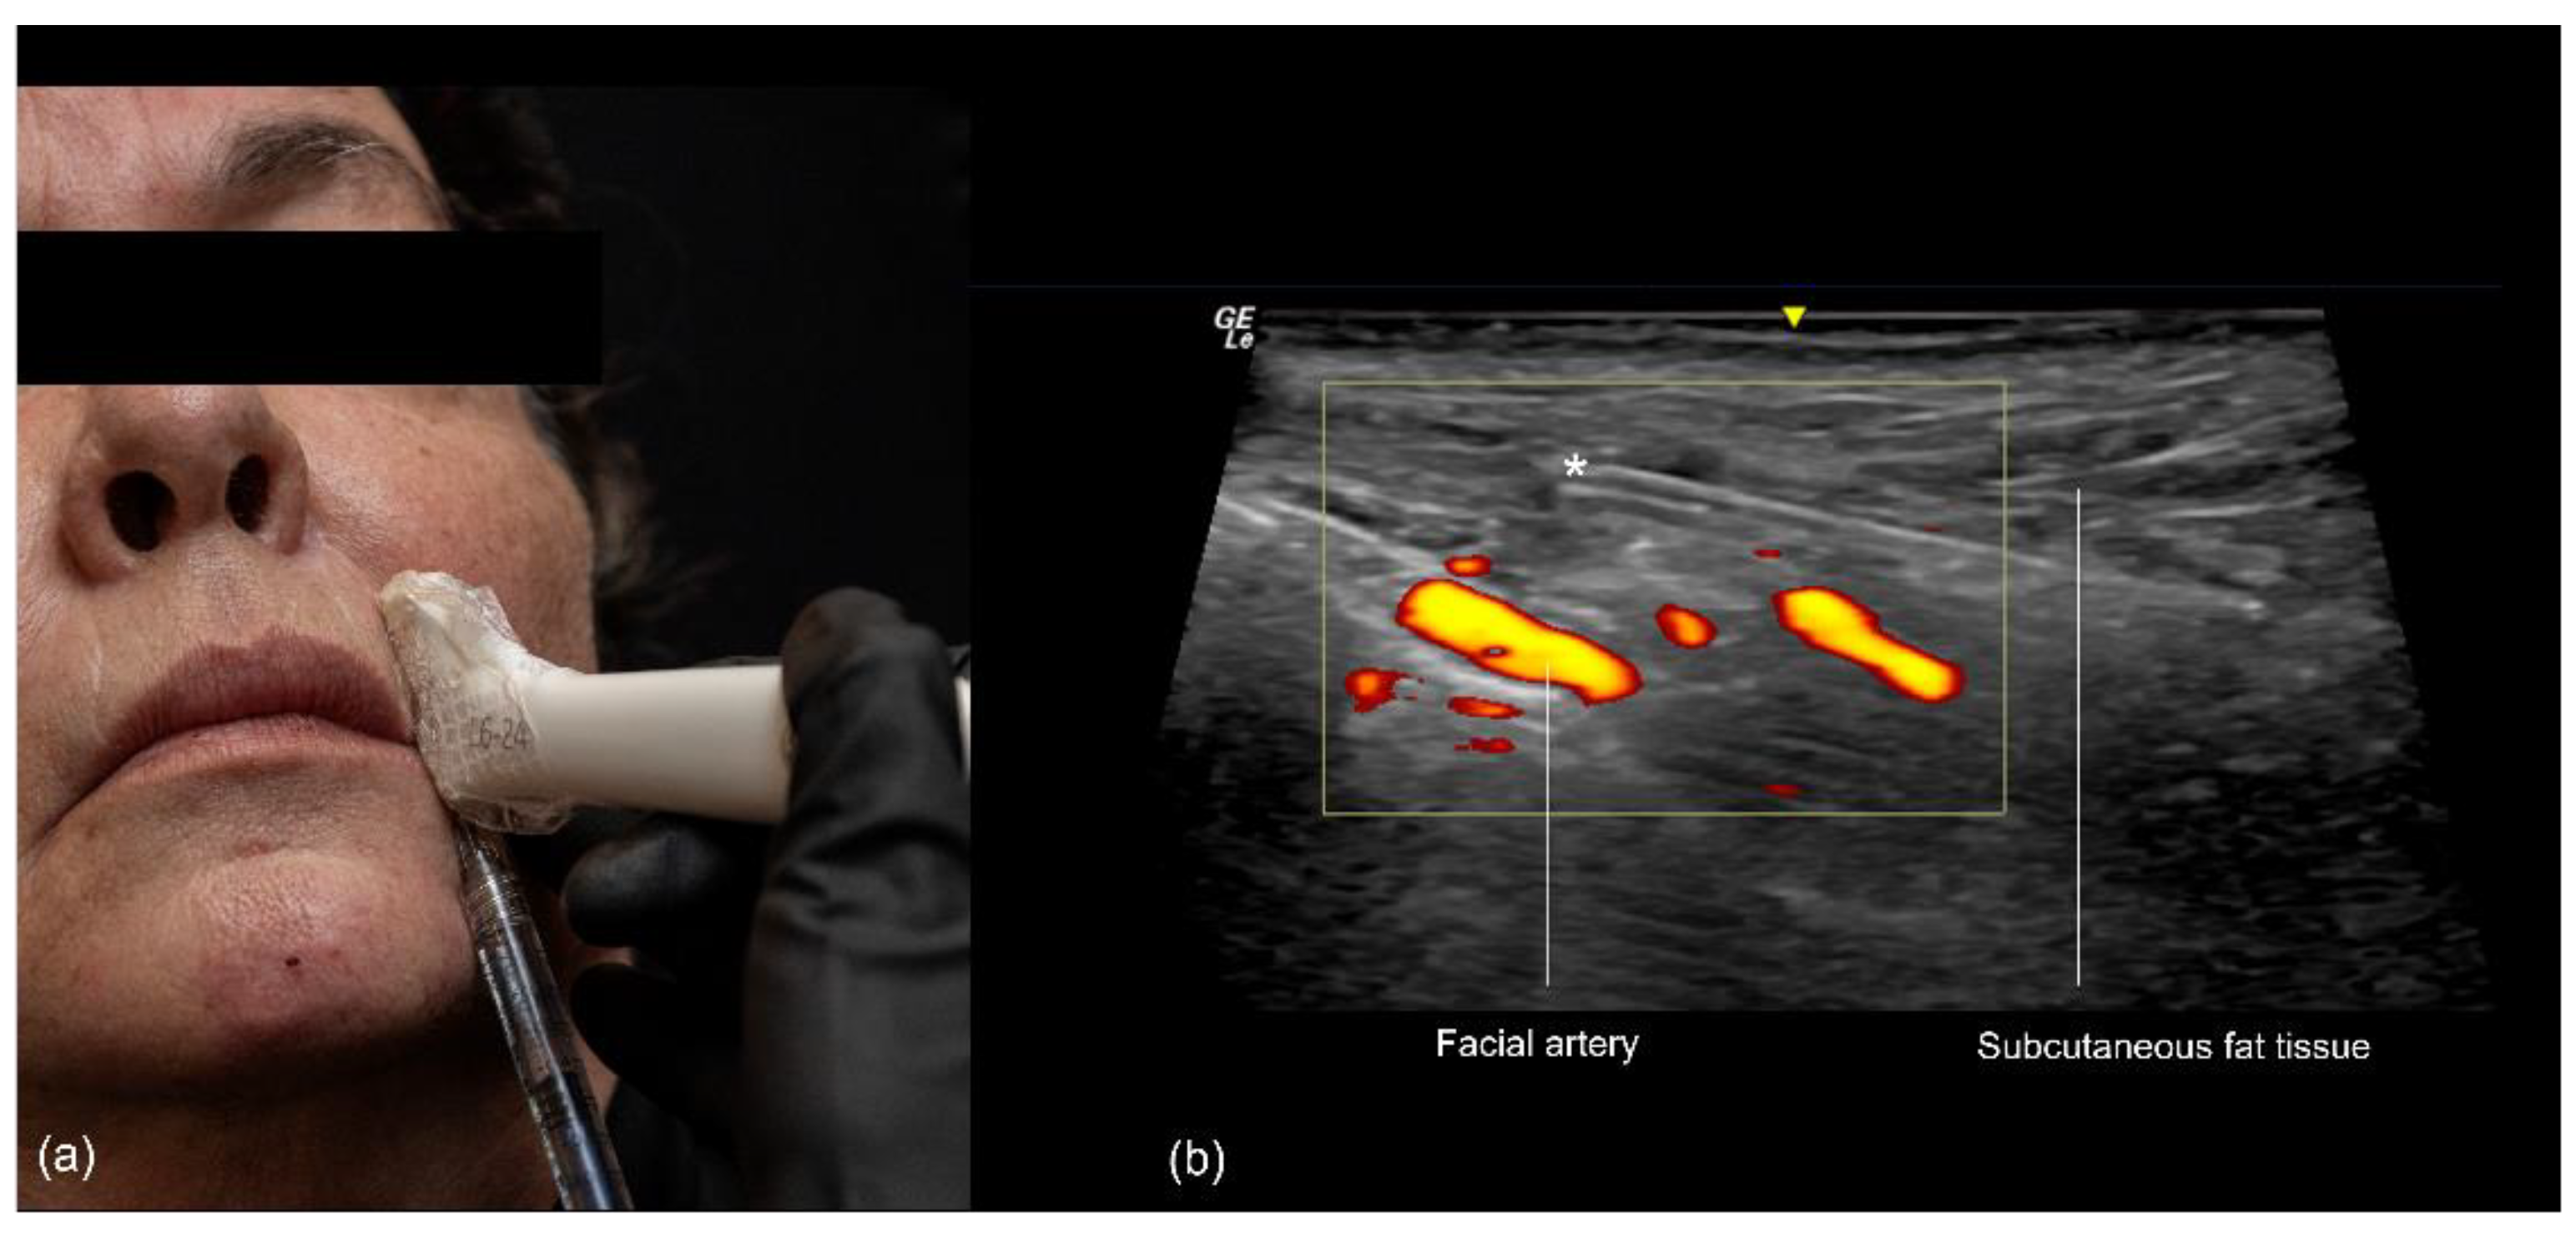

3.3. Nasolabial Fold

3.3.2. Ultrasound-Guided Filling Techniques of the Nasolabial Region

- Technique 1: Subcutaneous filler placement with a blunt cannula

- Technique 2: Supraperiosteal filler placement with a needle